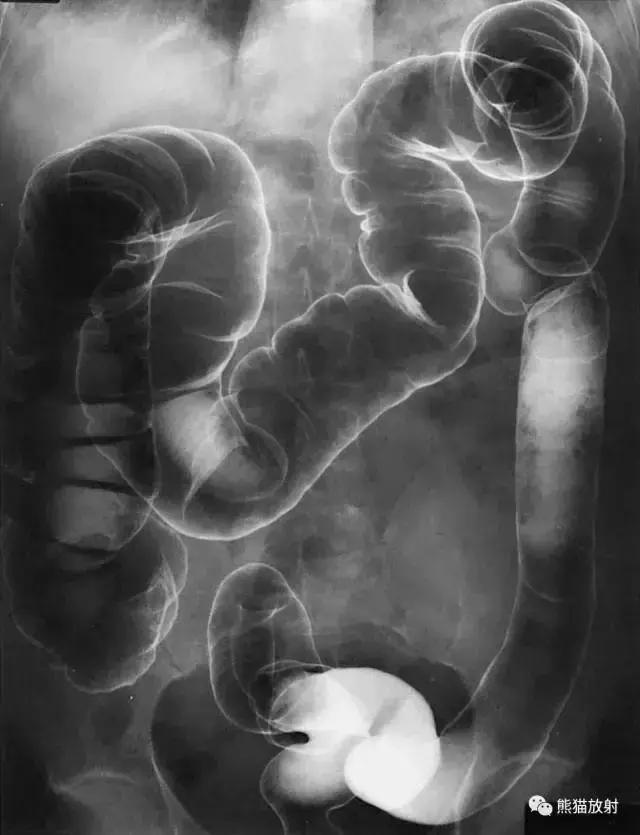

十、结肠

图19 结肠造影

图20 1 结肠脾曲,2 结肠肝曲,3 升结肠,4 横结肠,5 降结肠,6 结肠袋,7 回盲瓣,8 盲肠,9 乙状结肠,10 阑尾,11 直肠